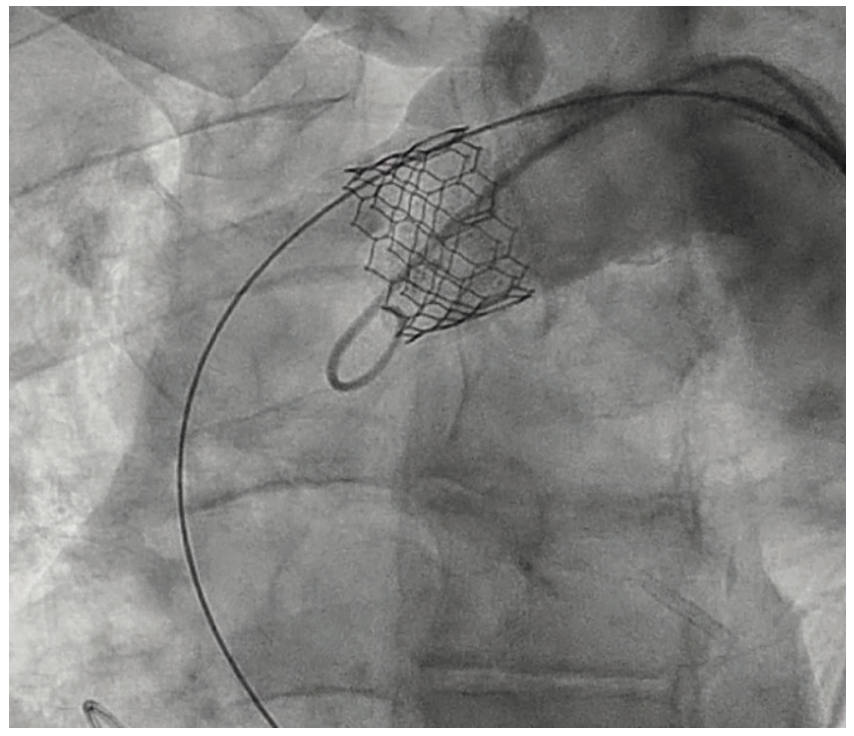

During the TAVR procedure, a Sapien 3 26 mm valve was loaded over a Safari wire (Boston Scientific) and advanced into the aortic annulus under fluoroscopy, with good planar angle positioning confirmed using contrast injection. After valve placement, rapid ventricular pacing was performed and the valve was deployed. However, immediately following deployment, the valve embolized into the ascending aorta. The valve was carefully pulled distally and secured just proximal to the origin of the right brachiocephalic artery. It was dilated with an extra 4 mL volume with two inflations performed. To confirm the patency of the right subclavian artery and the right brachiocephalic artery, access was subsequently obtained in the right radial artery, and no difference in the arterial pressure was noted as the catheter was advanced from the right radial artery into the aortic root. A second Sapien 3 26 mm valve was then loaded over the Safari wire and was similarly advanced into the aortic annulus under fluoroscopy, with good coplanar angle positioning confirmation via contrast injection. After rapid ventricular pacing, the second valve was deployed without issue. A post procedure aortogram confirmed good valve positioning, the absence of significant paravalvular leak, and patency of the left coronary artery. A limited echocardiogram also confirmed good valve positioning, the absence of paravalvular leak, and the absence of pericardial effusion. The patient tolerated the procedure well and left the cardiac catheterization laboratory in a stable condition. After chest x-ray confirmed stable positioning of the embolized valve in the ascending aorta, the patient was discharged on postoperative day one with a scheduled follow-up visit in three weeks.